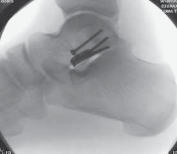

TECHNIQUES B C TECH FIG 1 • A. Bone model highlighting medial intra-articular, lateral extra-articular, and posterior screw fixation. B. Hawkins type II fracture. A C. Postoperative fixation.